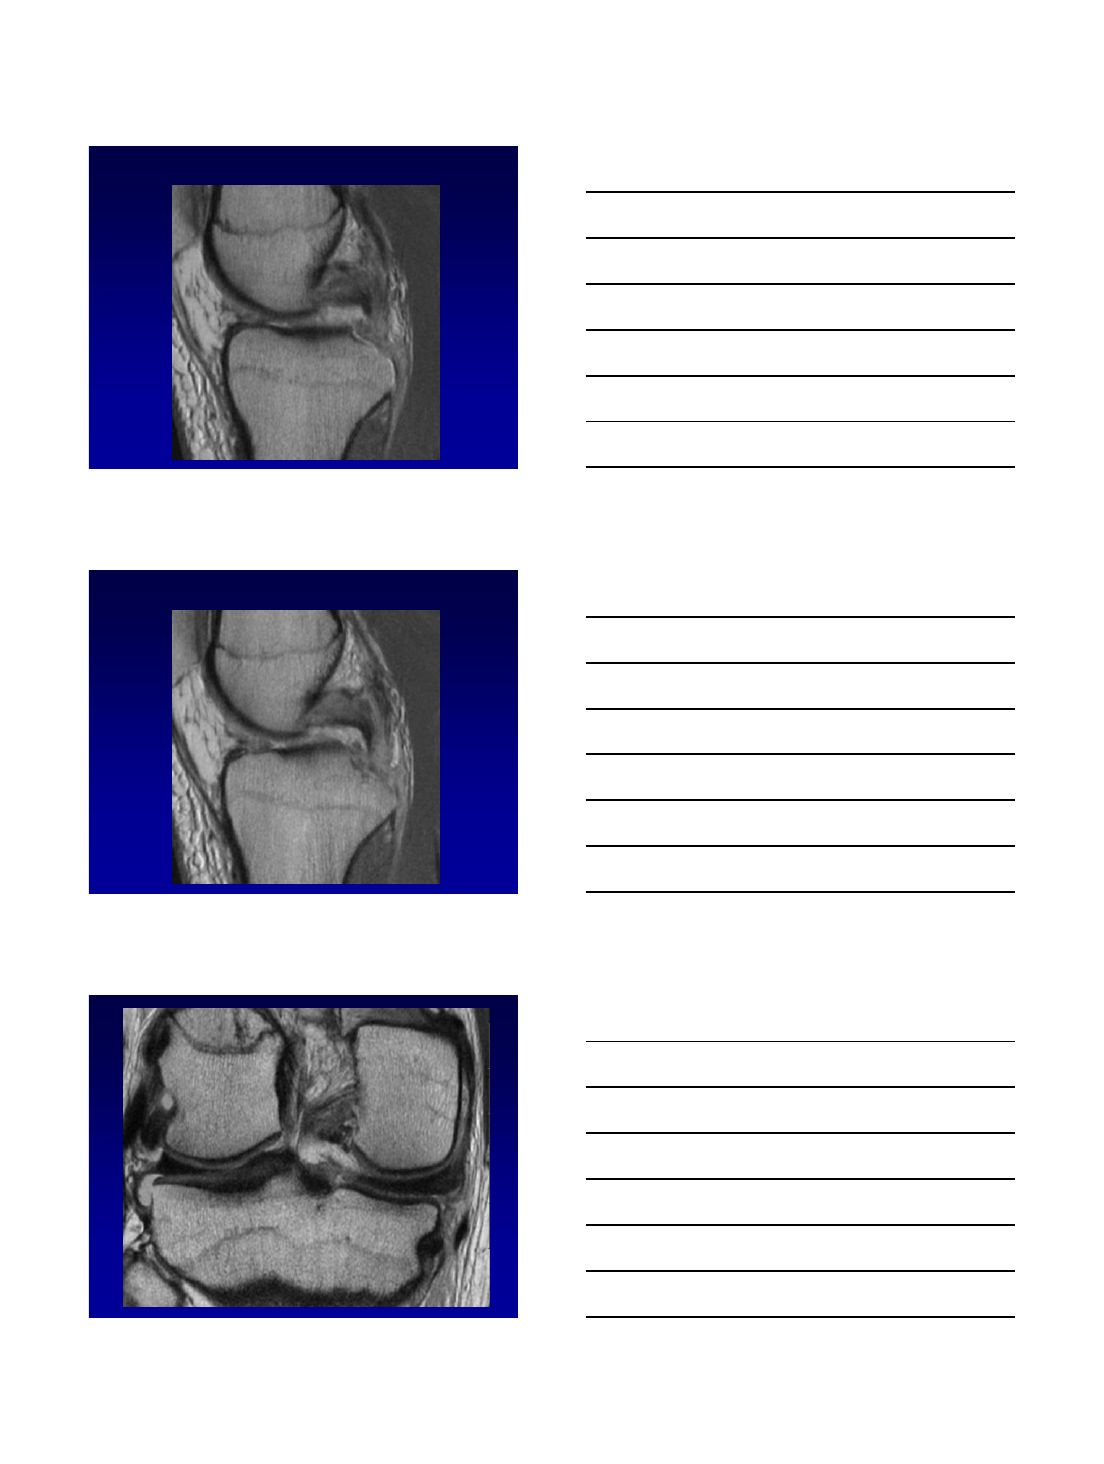

Bucket handle

•Circumferential longitudinal vertical tear

w/ displacement of free internal fragment

into intercondylar notch

•MM > LM

•MRI Signs

–Double PCL

–Double delta (lateral)

–Large AH

–Fragment in notch

–Absent bow tie

–Disproportionate horns

Double PCL

Double delta

Large AH

48 year-old man with medial knee pain.

Twisting injury a few months ago, heard a

“crack”.

10/13/2015